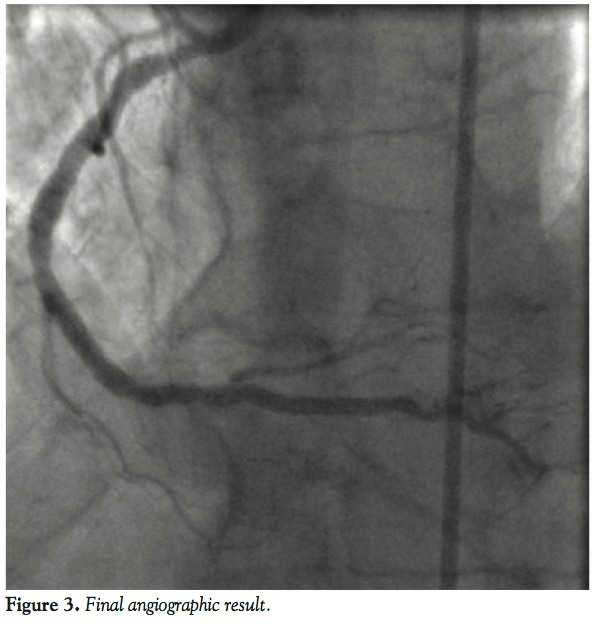

Coronary angioplasty was performed using a 7 Fr Amplatz Left I guiding catheter. Although the guiding catheter was not coaxial with the vessel, it allowed advancement of a 0.014´´ Balance Middleweight guidewire (Guidant Corporation) into the vessel, which redirected the tip of the catheter into coaxial engagement with the vessel. After advancing the guidewire at the distal vessel, multiple inflations of a 2.0 mm x 15 mm balloon were performed (up to 18 atm). Although the balloon easily crossed the lesion, it was not possible to advance a 2.5 mm x 20 mm Pl-Cr everolimus-eluting stent (Promus Element) at the distal lesion, due to insufficient backup support and heavy calcification. A 0.014 mm buddy wire (BHW, Guidant Corporation) was advanced across the lesion into the distal LAD to increase support and straighten the vessel. However, the stent was still unable to pass through successfully. We elected to aid stent delivery by performing extra deep intubation using the Guideliner 6 Fr catheter (mother and child technique). Using an inflated balloon in the distal lesion as an anchor, the Guideliner was advanced into the distal vessel. The tip of this catheter passed easily through the proximal segment, protruding by 4.1 cm into the RCA and allowed successful delivery of the stent at the distal lesion without resistance (Figure 2B). The procedure was completed by implanting 2 more non-overlapping stents (3.0 mm x 20 mm and 3.0 mm x 20 mm Promus Element stent) (Figures 2C and 2D) through the Guideliner catheter at the lesions of the mid portion of the vessel. A final postdilatation of the stents with a non-compliant balloon completed the procedure with an excellent angiographic result (Figure 3).